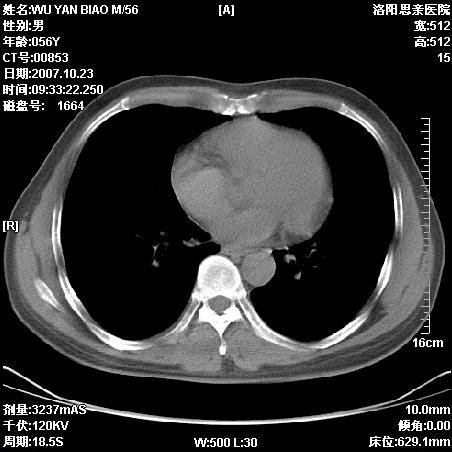

标题: CT10160:M56Y,体检发现,病人无不适,病人随访中 [打印本页]

标题: CT10160:M56Y,体检发现,病人无不适,病人随访中

后上纵隔占位,与肺交界清,宽基底附着脊柱,密度均匀,局部骨质无明确改变.

考虑;神经源性肿瘤,---起源交感n链?,不除外肠源性囊肿.

与纵隔关系密切,密度均匀。只能考虑:后纵隔神经原性肿瘤!

1、病灶在后纵隔脊柱旁沟内,此处是神经原性肿瘤的好发部位

2、病灶边缘光滑整齐,更说明病灶来于纵隔,由于有胸膜的包裹所以才导致这么光滑的边缘

3、病灶内的密度均匀